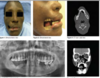

What is this infectious diseease?

What is its pathogensis ?

HSV‐1: Primary

Infection

pathogensis

❏ Usually young age

❏ Often asymptomatic

❏ Symptomatic = Primary herpetic gingivostomatitis

❏ In adults is usually pharyngotonsillitis (back of throat)

❏ Spread through infected saliva or active lesions

❏ Incubation period = 3‐9 days